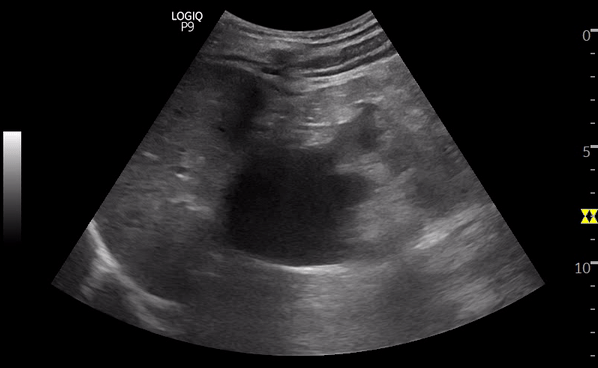

Hydronéphrose sévère

Dilatation majeure, calices largement ouverts

Amincissement du parenchyme rénal

Rein globuleux, architecture altérée

Hydronéphrose sévère. © POCUS Atlas

➡️ Plus l’hydronéphrose est marquée, plus l’obstruction est significative ou prolongée.